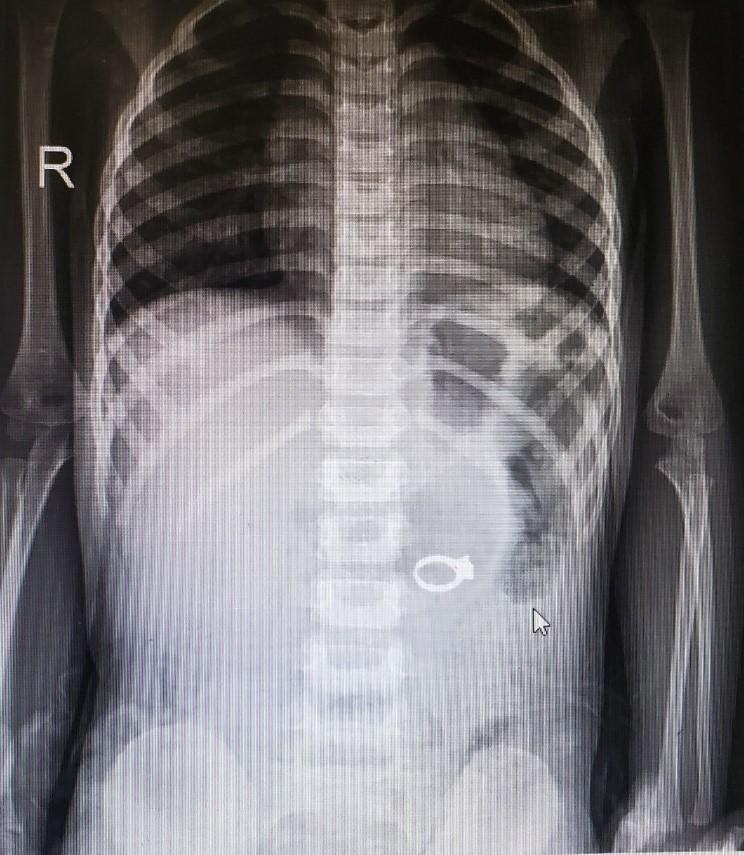

( Hình ảnh chụp Xquang )

Kết quả chụp X-quang cho thấy hình ảnh dị vật nằm ở vị trí tá tràng, kích thước khoảng 3cm.